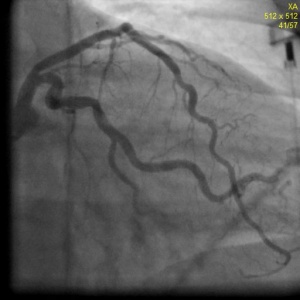

Пациентка Н. 61 года поступила в РКНПК МЗ РФ с клиникой стенокардии III-IV ФК, сохраняющейся на фоне многокомпонентной антиангинальной терапии в условиях ограничения физической активности. При МСКТ коронарных артерий определялись кальцинаты в проекции стенок коронарных артерий: в среднем сегменте ПНА объемом 25 мм³, КИ – 28 ЕД, в проксимальном сегменте ОА объемом 12 мм³, КИ 12 ЕД, во всех сегментах ПКА 21 мм³, КИ -24 ЕД. Суммарный КИ = 64 ЕД. При коронарной ангиографии от 5.12.12 года: сбалансированный тип коронарного кровоснабжения. Ствол левой коронарной артерии не изменен. Передняя нисходящая артерия (ПНА) в проксимальном сегменте с переходом на средний сегмент стенозирована на 71-91% (рис. 6) при компьютерном анализе (QCA), далее имеет гемодинамически незначимые неровности контуров. Огибающая артерия (ОА) имеет неровности контуров в среднем сегменте, артерия тупого края не изменена. Правая коронарная артерия с неровными контурами на всем протяжении, без гемодинамически значимого стенозирования. Во время коронарной ангиографии было проведено измерение фракционного резерва кровотока (ФРК) в ПНА и ОА. ФРК в среднем сегменте ПНА = 0.64, в дистальном сегменте ОА = 0,97. Под местной анестезией раствором лидокаина 2%-10 мл правым радиальным доступом был установлен интродюсер 6F. К устью левой коронарной артерии подведен направляющий катетер PB 3,5 и в дистальный сегмент ПНА проведен интракоронарный проводник. После ряда предилатаций баллонными катетерами 3,0х20 и 3,5х20 мм, было выполнено внутрисосудистое ультразвуковое исследование (ВСУЗИ): в проксимальном и среднем сегменте ПНА определяется гетерогенная эксцентрическая атеросклеротическая бляшка с признаками кальциноза, сужающая просвет на 72,1% площади (рис.7) , протяженностью 37 мм, должный диаметр ПНА в проксимальном и среднем сегменте 3,7 мм. В проксимальном и среднем сегменте ПНА последовательно установлены два биорастворимых сосудистых каркасов Absorb 3,5х28 и 3,5х12мм, давлением до 14 атмосфер, длительностью до 30 сек. Выполнена постдилатация БСК баллонным катетером 3,5х20мм, давлением до 18 атм, длительностью до 30 сек (Рис.8). При контрольном ВСУЗИ в проксимальном и среднем сегменте ПНА определяются БСК полностью расправленные, без признаков пристеночного тромбоза и краевых диссекций. Диаметр просвет артерии в месте установки БСК 3,7 мм (Рис.9). Проводник, катетер и интродюсер удалены выполнен гемостаз места пункции, наложена тугая асептическая повязка. После вмешательства приступы стенокардии не рецидивировали, через 2 дня пациентка была выписана домой в удовлетворительном состоянии.

Рисунок 6. Левая коронарная артерия. Стеноз проксимального и среднего сегмента передней нисходящей артерии.